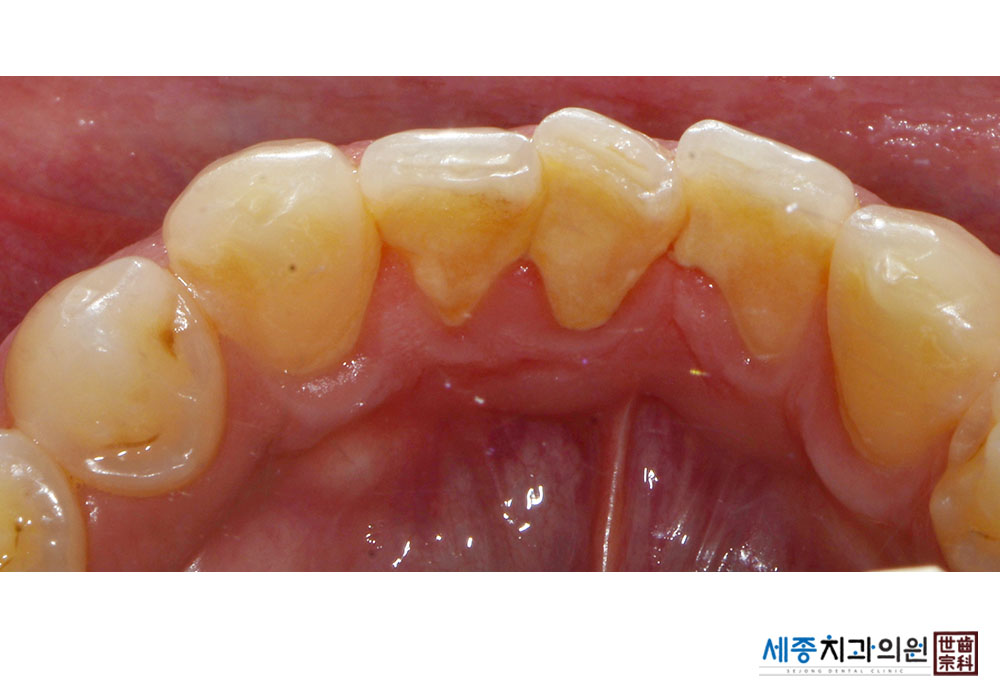

[스케일링] 치주질환 예방 스케일링

치료전 : 2022-08-22

가글마취&저주파 스켈러를 사용한 스케일링